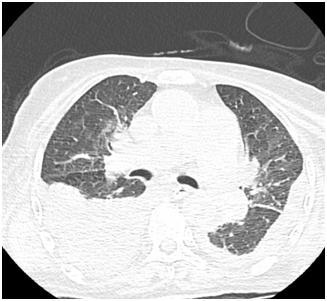

![]() | ![]() |

Двусторонний гидроторакс (компьютерная томография органов грудной клетки).